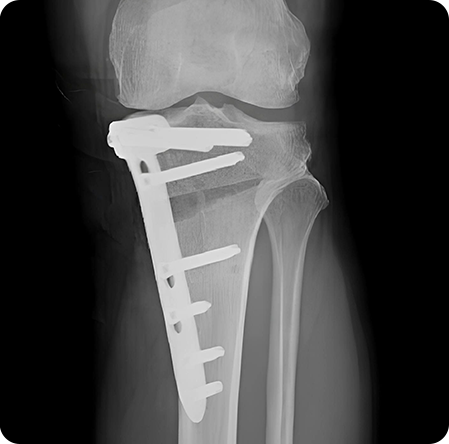

종아리뼈 일부를 절골한 후, 수술 기구를 이용하여 필요한 각도만큼 뼈를 벌려

금속판과 나사를 이용하여 고정합니다.

경골을 절골하여 원하는 각도로 벌려 무게 중심이

바깥쪽으로 옮겨지도록 교정

합니다. 절골한 부위를

금속판과 나사로 고정해 뼈가 안정적으로 붙도록 합니다.